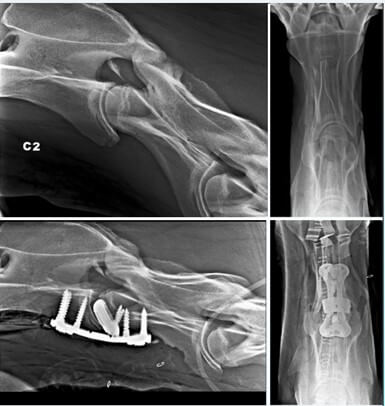

Während der Operation wird das Pferd anästhesiert und in einer chirurgischen Hängematte immobilisiert. Eine mit dem 3D-Drucker hergestellte Platte und 3D-gedruckte Spongiosaschrauben stabilisieren den Bruch und überbrücken die Wirbel. Abhängig von den betroffenen Wirbeln wird im ventralen Bandscheibenbereich ein kleiner 3D-gedruckter Cage aus Titan eingesetzt.

Zur Kompression des gebrochenen Fragments wird manchmal eine Kombination aus Spongiosa- oder Kortikal- und Verriegelungsschrauben verwendet. Dadurch kann ein mit 3D-Druck hergestellter Bandscheiben-Spacer aus Titan mit seiner Kompressionskraft den Abstand zwischen den Wirbeln aufrechterhalten. Das verhindert, dass die Bandscheibe in den Markkanal ragt und der kaudale Wirbel sich ventral verschiebt.

Zusammenspiel von Schrauben und 3D-Druck-Platte

Die Form der Platte ermöglicht die Platzierung der drei Schrauben in jedem Wirbel. Titan-Implantate ermöglichen eine bessere Osseointegration als Stahlimplantate. Mit dem Metall-3D-Druck können poröse Strukturen angefertigt werden, die das durch den Cage hindurch und die Fixierung des Knochens am Cage erleichtern.

Bisher sind bei diesem Eingriff, der unter Röntgen- oder Durchleuchtungskontrolle durchgeführt wird, nur wenig Komplikationen aufgetreten, wie die Bildung von Seromen oder das Lösen von Schrauben. Diese Methode ist bei zervikaler Arthrodese oder im Fall eines Traumas geeignet, aber auch bei Fehlstellungen.